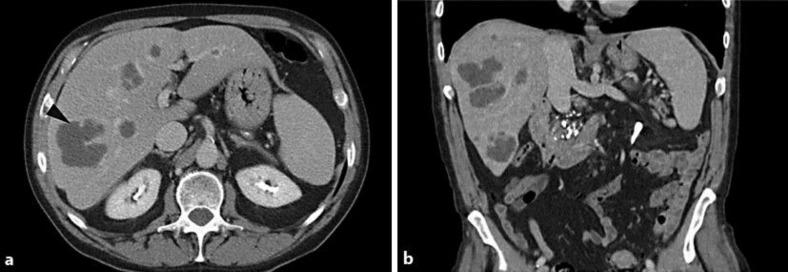

Fusobacterium is well characterized as an oropharyngeal pathogen that may induce a septic thrombophlebitis by direct extension of abscess into an adjacent neck vessel (Lemierre's syndrome); its potential for visceral abscess formation, however, remains under-recognized. A 65-year-old man with a recent history of multiple rim-enhancing liver lesions presented to the emergency room with fever and abdominal pain. Based on interval increase in the size of the lesions, abscess was suspected. A liver biopsy was performed, and although no organism could be identified on routine microscopy, Warthin-Starry stain revealed Gram-negative bacilli consistent with an anaerobic Fusobacterium species as the underlying etiology of liver abscess formation. Subsequent anaerobic culture results confirmed the diagnosis. This case highlights the importance of consideration for Fusobacterium infection in the setting of liver abscess if anaerobic organisms have not yet been excluded on initial culture evaluation.

梭杆菌作为一种口咽病原体已得到充分认识,它可通过脓肿直接蔓延至邻近颈部血管而诱发脓毒性血栓性静脉炎(勒米尔综合征);然而,其形成内脏脓肿的可能性仍未得到充分认识。一名65岁男性,近期有多个环形强化肝脏病变病史,因发热和腹痛就诊于急诊室。基于病变大小的间隔性增大,怀疑为脓肿。进行了肝脏活检,尽管常规显微镜检查未发现病原体,但沃辛-斯塔里染色显示革兰氏阴性杆菌,与厌氧梭杆菌属一致,为肝脓肿形成的潜在病因。随后的厌氧培养结果证实了诊断。该病例强调了在肝脓肿情况下,如果初始培养评估尚未排除厌氧生物,考虑梭杆菌感染的重要性。